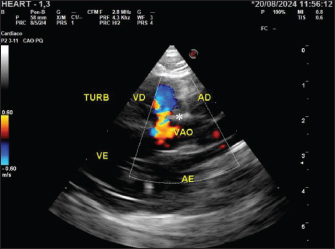

Shortly after the second visit, the patient was referred for emergency care due to cyanosis, expiratory dyspnea, and mild tachycardia. Furosemide (Teuto, Anápolis, GO, Brazil) was administered intravenously (IV) at a dose of 2 mg/kg along with fluid therapy (3 ml/kg/hour). In addition, the patient was hospitalized for monitoring respiratory pattern and vital parameters. Once the condition had stabilized, a new echocardiogram was performed with a microbubble test, which was negative and confirmed the diagnosis of VSD (Fig. 2). During the examination, the patient presented with a second episode of cyanosis and expiratory dyspnea, followed by respiratory arrest while in the lateral decubitus position. Consequently, left lateral, right lateral, and dorsoventral survey X-rays of the thoracic region were obtained, which indicated PPH (Fig. 3).

Fig. 2. Echocardiogram of the patient at 60 days, showing turbulent flow (*) in B-mode, in the perimembranous ventricular region in a longitudinal section with a negative microbubble test. TURB, turbulent flow; RV, right ventricle; LV, left ventricle; VSD, ventricular septal defect; RA, right atrium; LA, left atrium.

The turbulent flow in the perimembranous ventricular region led to the diagnosis of VSD with left-to-right flow, which is common in the early stages of heart disease (Fernandes et al., 2019; Coelho et al., 2020; Pacó et al., 2022). Therefore, the prognosis for patients with this condition can still be considered favorable, as it does not have significant systemic repercussions and does not directly affect the quality of life, unlike what occurs when there is a reversal of the flow from right to left (Coelho et al., 2020; Perdoncini and Gusso, 2022). Given this, and the fact that there was no hypertension or cardiac remodeling, despite the overload of the right ventricle, no pharmacological treatment was indicated for the patient.